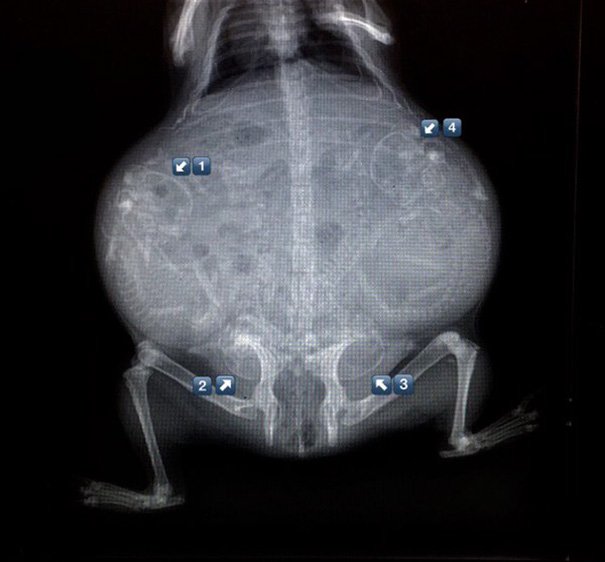

Итак, как выглядят рентгеновские снимки беременных животных:

ещё одна морская свинка